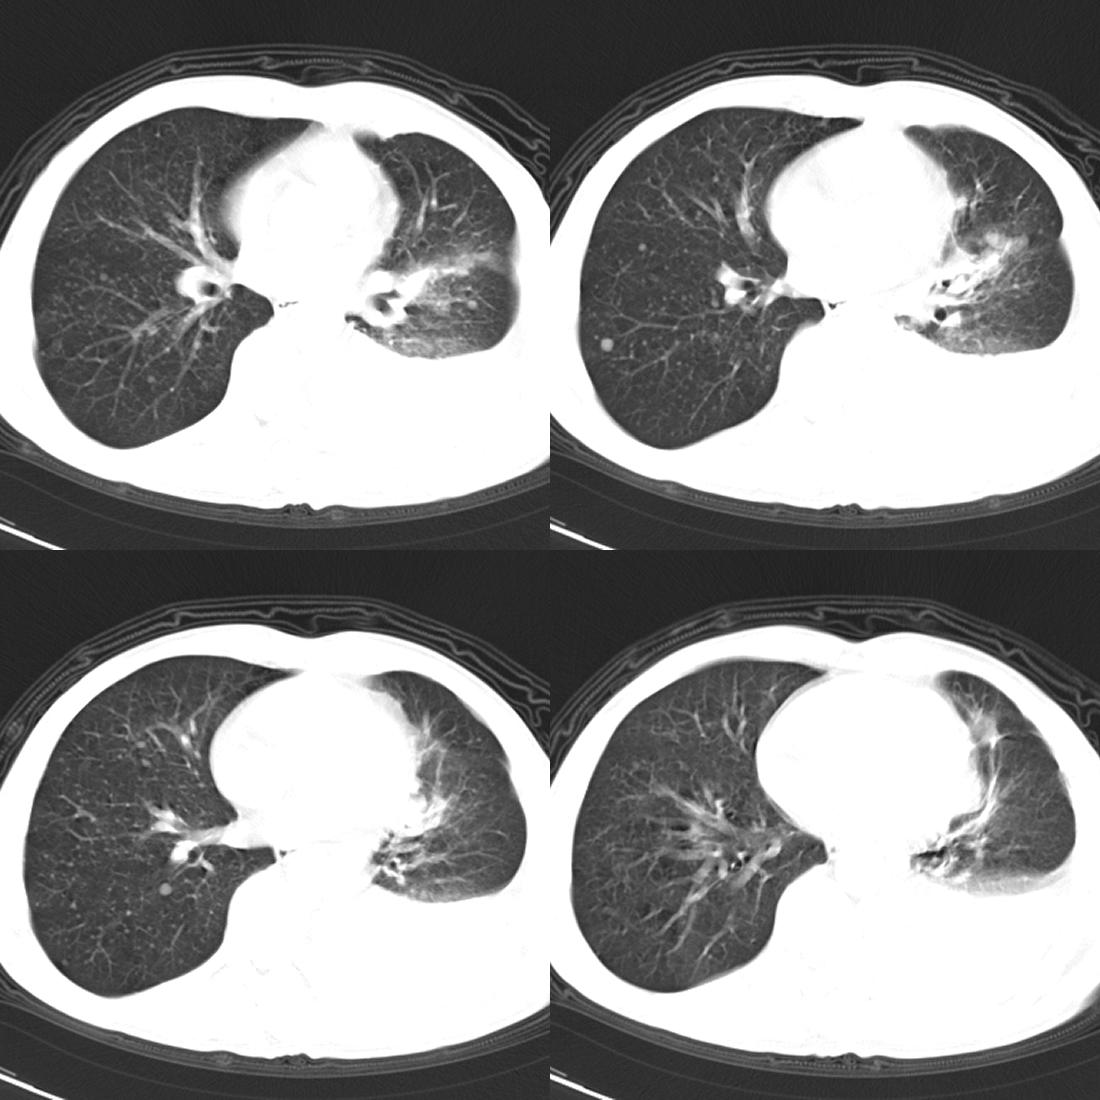

左肺上叶周围型肺癌伴肺\\胸膜\\肋骨\\胸椎横突转移,左侧胸腔积液.

左侧椎体、横突、肋骨呈溶骨性破坏,半左侧胸腔中等量积液;左肺尖部可见一肿块影,边界欠清;多考虑恶性骨肿瘤,不除外肺尖部转移性表现可能。

左肺上叶周围型肺癌伴双肺\\胸膜\\肋骨\\胸椎横突转移,左侧胸腔积液.

左肺上叶周围型肺癌伴肺\\胸膜\\肋骨\\胸椎转移。

左肺上叶周围型肺癌伴肺胸膜肋骨胸椎横突转移,左侧胸腔积液。